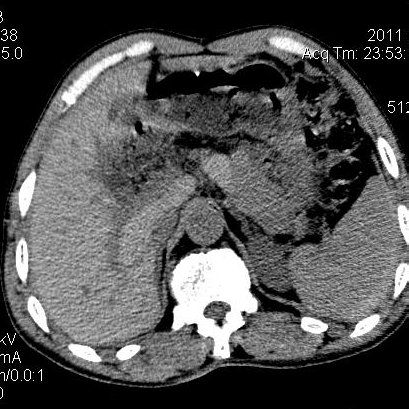

肝左叶发育异常

男性,55岁,骑摩托车摔倒后入院,自述右上腹疼痛

[backcolor=#FF0000]第一次诊断的时候也是这么肯定,可是床旁超声检查并没有发现明显异常,而且患者的一般症状都良好。还好临床只是保守治疗,没有立即手术,第二次复查的时候没有一点变化,又做了MRI检查,没有血肿,

这是一例肝左叶发育异常的,很个性吧~[/backcolor]